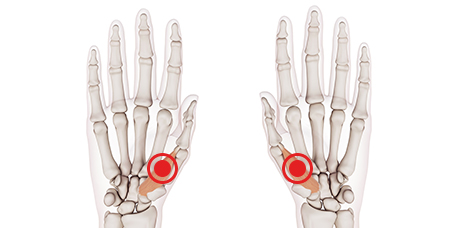

손목건초염 (드퀘르병)

손가락 힘줄을 싸고 있는 건초에 염증이 발생한 질환

방아쇠수지 (손가락 힘줄염)

손가락을 굽히는 힘줄에 염증이 발생한 질환